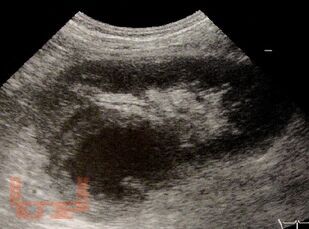

В учебном пособии отражены сведения, касающиеся, методики ультразвукового исследования и ультразвуковой семиотики опухолей почек и мочеточников. Особое внимание уделяется использованию метода в первичной, дифференциальной и уточняющей диагностике у онкоурологических пациентов.